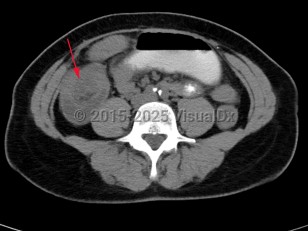

Intussusception in Adult

Intussusception is a telescoping or invagination of a part of the intestine into the lumen of an adjacent segment. Intussusception can present with variable severity. It can present with bowel ischemia and perforation with need for emergent surgical intervention, or it can present as relaxing / remitting abdominal pain of unclear etiology with intermittent symptoms and no signs of systemic illness. Jejunojejunal, jejunoileal, ileoileal, ileocolonic, and colocolonic are all types of intussusception that can occur, with the majority involving the small intestine.

Intussusception in adults presents with similar symptoms: sudden-onset abdominal pain that can relax and remit, with or without symptoms of acute bowel obstruction and hematochezia. Intussusception in adults can also be caused by viral infections, polyps, or postsurgical adhesions, but there is greater concern for underlying malignancy – either small or large bowel or extrinsic (eg, lymphoma) – as a trigger point.

Initial management requires ensuring hemodynamic stability, as many patients are dehydrated, and assessing concern for bowel perforation, which could require broad-spectrum antibiotics and urgent surgical intervention. Air or barium enemas can be both diagnostic and therapeutic. However, intussusception will frequently recur, in which case surgical resection is often required. Further imaging (ie, small bowel x-ray series, CT or MRI abdomen) can be utilized to identify the etiology if it is unknown based on presenting symptoms and a barium / air enema.